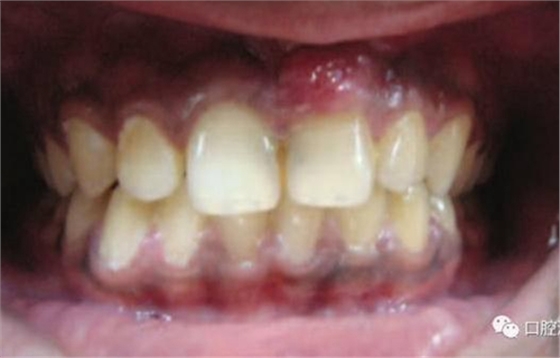

11、21 治療前

對瘺管位置進(jìn)行激光氣化